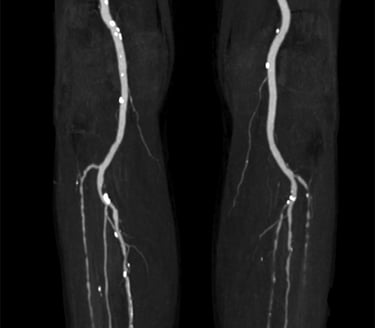

Leg Circulation& Peripheral Artery Treatments

Poor circulation in your legs can signal heart disease. Through peripheral angioplasty, limb salvage procedures, and endovascular therapies, Dr. Anil restores blood flow, prevents amputation, and improves mobility and quality of life.